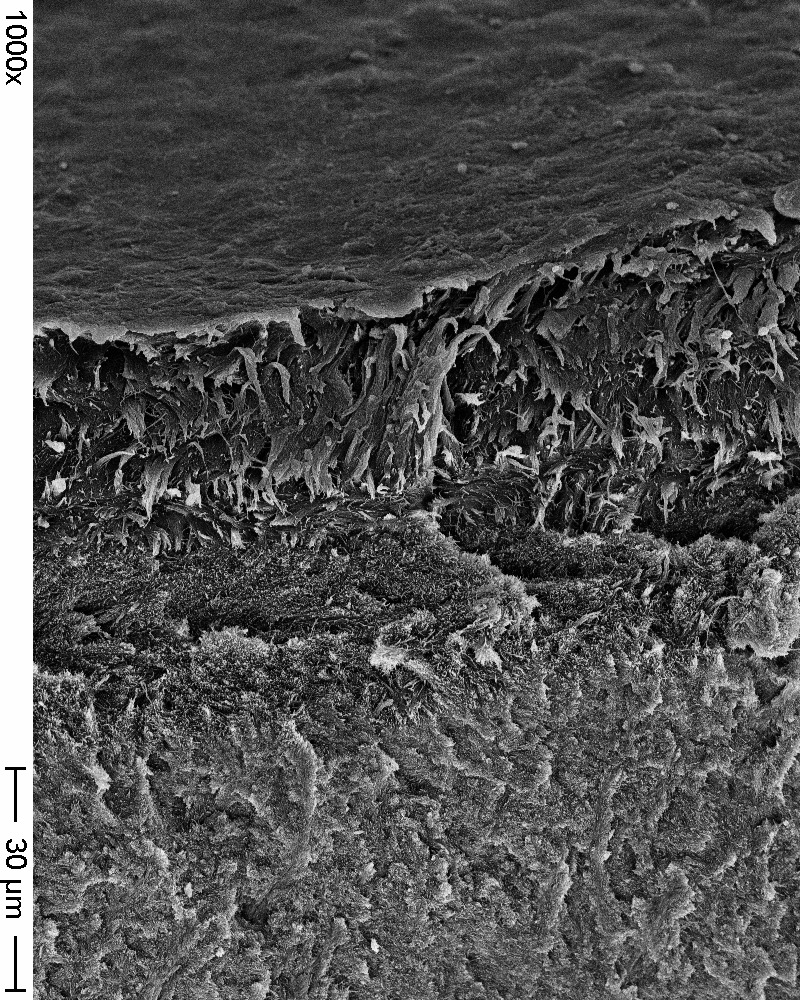

Methods: A total of 128 enamel disks obtained from anterior human teeth and 128 disks with the same dimensions were obtained from a nanohybrid resin-based composite (RBC, Clearfil Majesty ES-2, shade A2, Kuraray Europe GmbH, Hattersheim am Main, Germany). Three toothpaste formulations were analyzed both on enamel and composite specimens: A) Toothpaste without active principle; B) Toothpaste containing hydroxyapatite nano-particles (Biorepair® Protezione Totale, Coswell, Italy); C) Toothpaste containing Mg-Ca-Sr biomimetic hydroxyapatite (Biosmalto®, Curaden Healthcare Spa, Italy). A control group (D) has been prepared for comparison. The specimens were placed in the MDFR device and then incubated at 37°C for 24 h in clarified saliva. In parallel, it was decided to carry out additional experiments developing mixed plaque and monospecific Streptococcus mutans biofilms inside microtiter plates, under static conditions.

Results: Enamel surfaces were generally less colonized than the RBC counterparts (p<0.0001). In particular, Group C was significantly less colonized than the control on both surfaces (p<0.0001). No significant differences were found between Group B and the control (p=0.8804 and p=0.6892 for RBC and enamel surfaces, respectively). and between Group A and the control on RBC surfaces (p=0.6855).